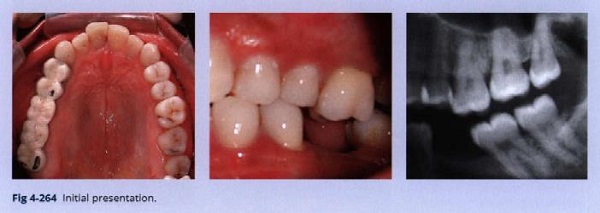

Bệnh nhân này có một răng hàm lớn thứ nhất hàm dưới bị mất và một răng hàm lớn thứ nhất hàm trên trồi xuống (Hình 4-264).

Chẩn đoán:

• Mất răng 36

• Trồi răng 26

• Chen chúc

• Cắn chéo phía trước ở răng 12